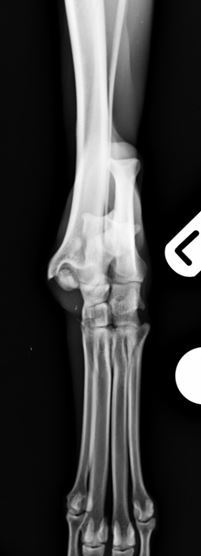

Radiographs revealed a comminuted non-reducible fracture of the medial talar ridge and a displaced fracture of the distal fibula.

Figure 2. Comminuted talar and distal fibular fractures craniocaudal view